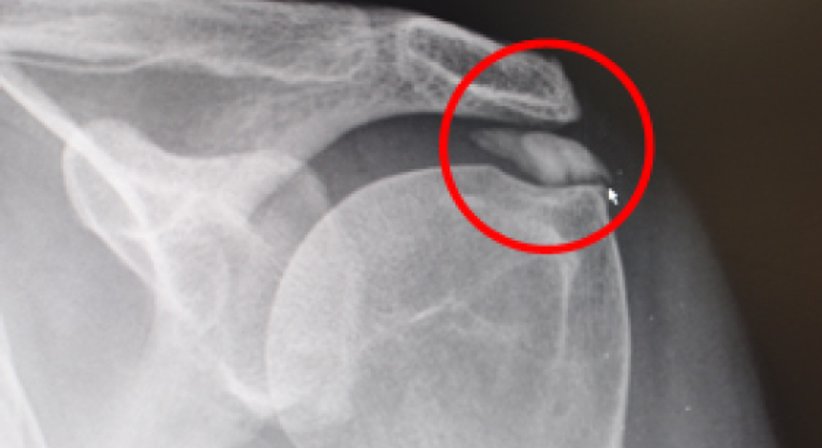

Um eine oft schmerzhafte Schultererkrankung handelt es sich bei der Tendinosis calcarea, der sogenannten Kalkschulter. Hierbei lagert sich Kalk in den Sehnen der Rotatorenmanschette ab. Im Rahmen der Diagnose können diese Ablagerungen meist im Röntgenbild oder durch eine Ultraschalluntersuchung sichtbar gemacht werden. Die Ursache für die Erkrankung ist noch nicht sicher geklärt, es werden jedoch mechanische, vaskuläre (durchblutungsbedingte) und biochemische Faktoren diskutiert. Die Erkrankung tritt vorwiegend zwischen dem 30. und 50. Lebensjahr auf. Frauen sind häufiger davon betroffen als Männer.